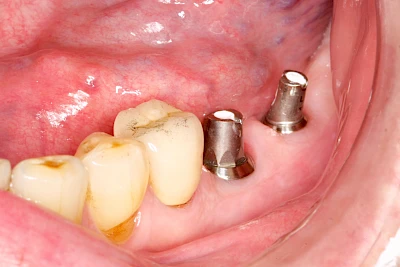

Fehlen einzelne Zähne und die Nachbarzähne sind unbeschadet oder gut zahnärztlich versorgt, werden immer häufiger Implantate gewählt, um die Lücken zu schließen. Auch bei größeren oder verteilten Lücken, wenn keine herausnehmbare Prothese gewünscht ist, werden Implantate für Kronen- bzw. Brückenversorgungen gesetzt. In Einzelfällen entscheiden sich sogar zahnlose Patienten für eine festsitzende Versorgung auf Implantaten.

Varianten zur Verankerung von festsitzendem Zahnersatz auf Implantaten